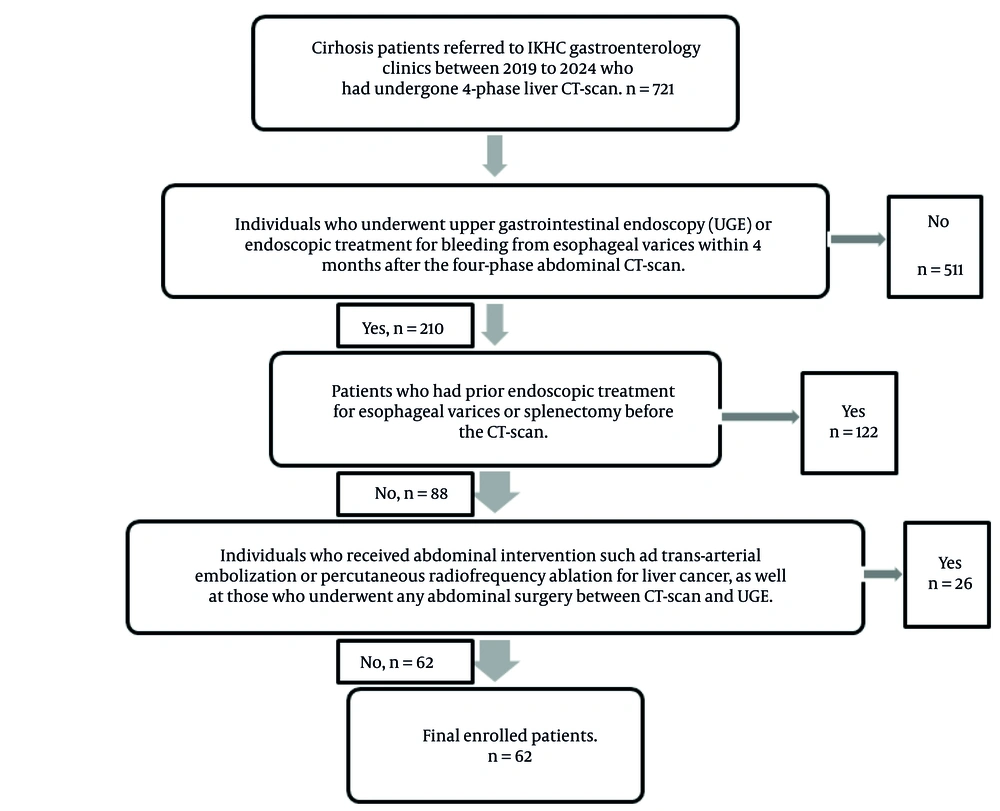

This case-control study included patients diagnosed with cirrhosis who were referred to the gastroenterology clinics of a tertiary referral hospital in Tehran between 2019 and 2024. Inclusion criteria comprised patients undergoing UGE or endoscopic treatment for esophageal variceal bleeding within four months of a four-phase contrast-enhanced abdominal CT scan. Patients were excluded if they had received abdominal interventions such as transarterial embolization or percutaneous radiofrequency ablation for HCC or had undergone any abdominal surgery between CT and UGE. Additional exclusion criteria included prior endoscopic treatment for esophageal varices or splenectomy before CT imaging. A total of 62 patients met all inclusion criteria and none of the exclusion criteria (Figure 1).